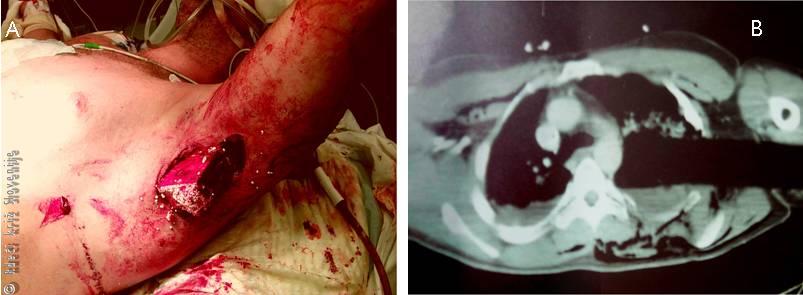

Slika 1

A – Položaj pljuč in pljučne mrene.

B – Gibanje prepone in prsnega koša pri vdihu in izdihu.